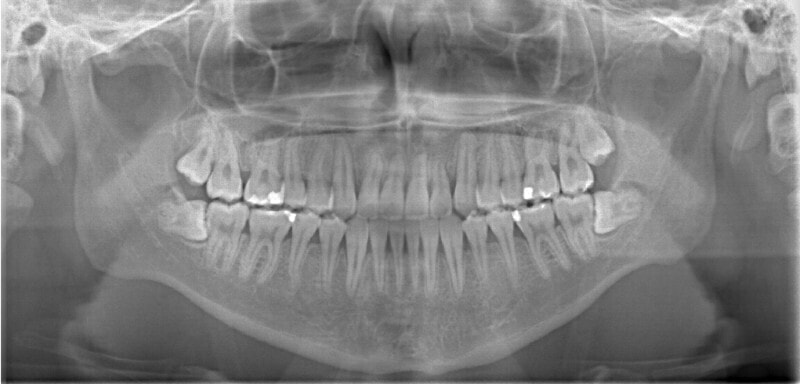

治療後(2年1ヶ月後)

解説:残存している左上乳犬歯Cを抜歯し、そのスペースに左上3番を誘導しました。Cと犬歯ではスペースが足りないので、前歯をアドバンスさせ、反対咬合を同時に解消しております。

下顎の右側への偏位は解消されました。

大臼歯は整直されております。

歯根のパラレリングは良好です。

左上2番の歯根も問題なさそうです。